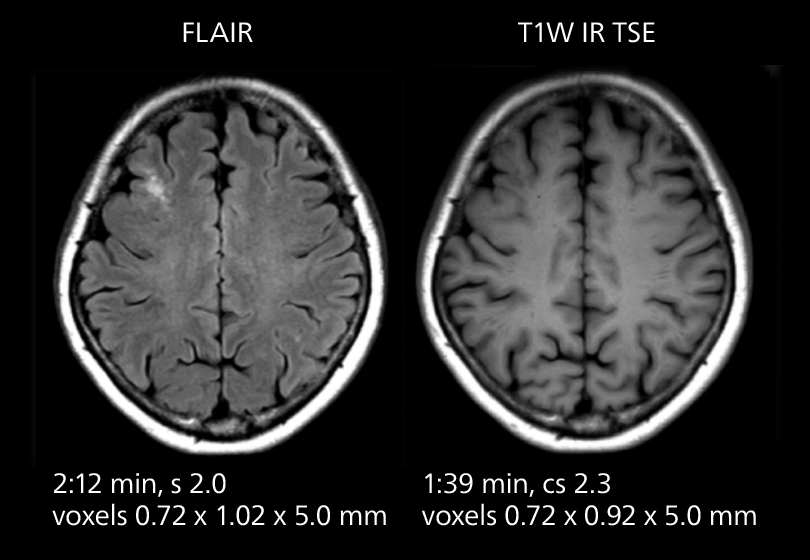

Brain MRI

These images of an old cerebral infarction demonstrate the speed and image quality after upgrading to Elition X.